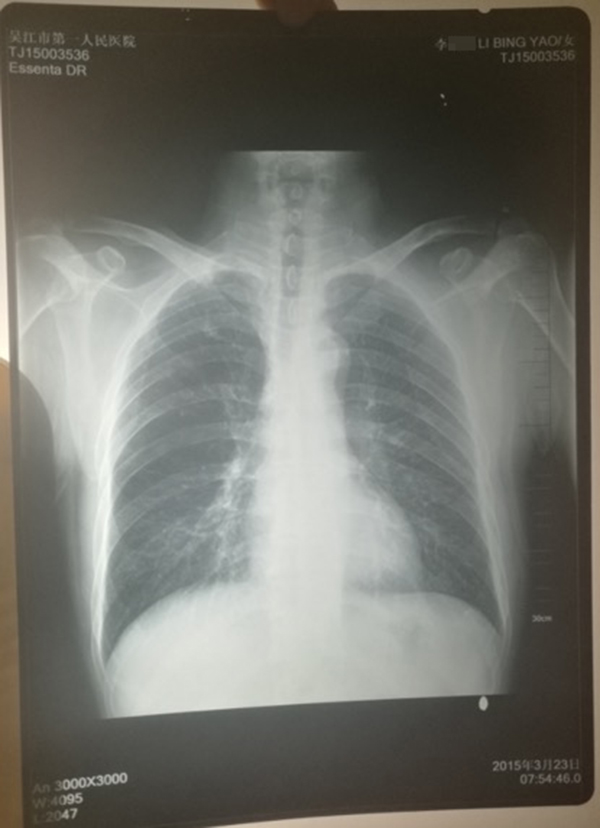

醫(yī)院提供的計建宏的“真實胸片”,寫有姓名“李某某”。 受訪人供圖

計云強稱,吳江區(qū)第一人民醫(yī)院曾提供一份印有“李某某”姓名的胸片,并稱該胸片才是計建宏的“真實影像結果”。

對于“李某某”姓名的胸片,上述吳姓主任稱,經過醫(yī)院核查,兩份胸片的結果都是“正常”的,“如果結果是不一樣的話,那么問題就大了,但是因為是一樣的結果,所以不能認為是‘漏診’或‘誤診’。”